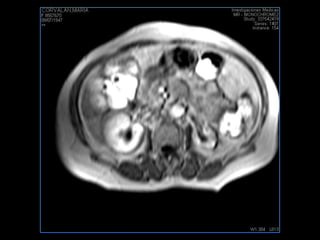

PROTOCOLO pancreas/ riñon AXIAL fat sat /AX in phase out phase AX T1 +SAG T2  COR T2, CON   GADOLINIO :  COR T1+AX T1(DIN) SAT: NO  FASE: RL THK: 4MM  COIL:  GAP: (FACTOR 1.4) 1MM FOV: 40 CM NEX:2 SINCRONIZACION RESPIRATORIA EN 3 O 4 CICLOS ALE